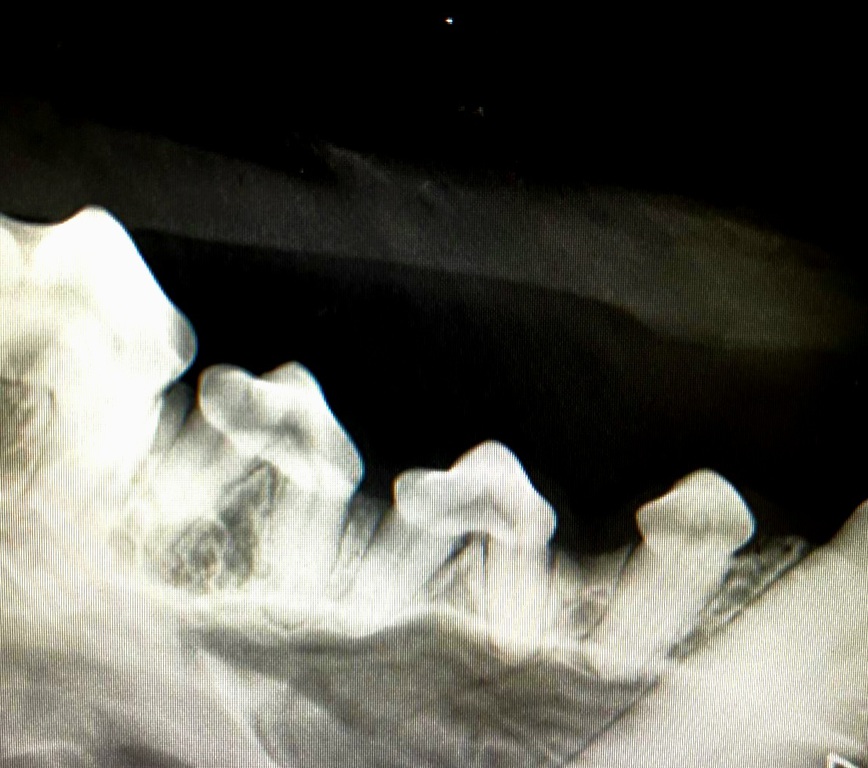

Zahnsanierung Kleintiere:

Aus der Maulhöhle unserer Lieblinge können die Bakterien in innere Organe absiedeln. Auch über deren Atem können diese an uns weiter gegeben werden. Deshalb sind gesunde Zähne wichtig für ein langes Leben unserer Tiere. Wir scheuen uns nicht auch sehr alte Tiere in Narkose zu legen. Häufig ist dies unererlässlich um tägliche Schmerzen in der Maulhöhle zu vermeiden. Lassen Sie sich gerne von uns beraten:

• Digitales Zahnröntgen

• Zahnsteinentfernung inklusive Politur

• Zahnsanierung

• Beratung über die Pllege der Zähne